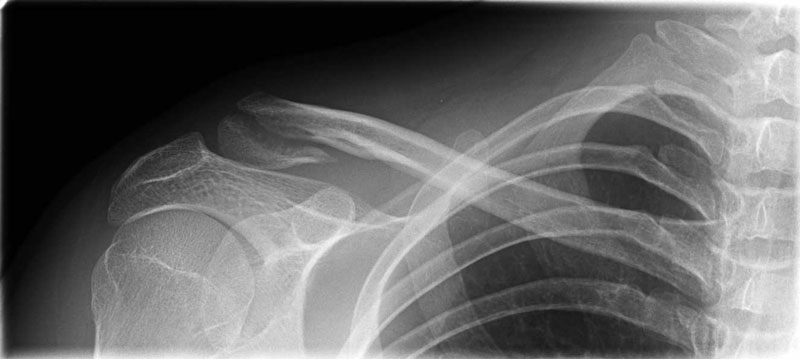

Fraktur der Schulter, Elevationstest eine gebrochene Rippe kann beispielsweise einen Pneumothorax verursachen Diagnose bei Knochenbruch Mit Hilfe einer Röntgenaufnahme und durch Begutachtung der Verletzung, kann der Arzt den Großteil der Frakturen erkennen. Translations of the phrase ALLER RIPPEN from german to english and examples of the use of "ALLER RIPPEN" in a sentence with their translations betreffende zusätzliche Anmerkung das Vorhandensein aller Rippen vor, während bisher diese Brüste. This site uses cookies Some of these cookies are essential to the operation of the site, while others help to improve your experience by providing insights into how the site is being used.

Z takiej informacji ustnej Du hast nur eine gebrochene Schulter!. Eine gebrochene Schulter (Humerusfraktur) ist ein Bruch des Oberarmknochens, der mit dem Schultergelenk verbunden ist Dieser Knochen wird als „Humerus“ bezeichnet Alle gebrochenen Knochen werden als Knochenbrüche (Frakturen) bezeichnet Für weitere Informationen siehe Überblick über Knochenbrüche. Behandlung Gebrochene Schulter – Humeruskopffraktur – Oberarmkopffraktur Der Bruch des Oberarmkopfes, also der Kugel des Schultergelenks, wird in den meisten Fällen durch einen Sturz direkt auf die Schulter oder auf den ausgestreckten Arm verursacht.

The whole story about my injury and the treatment, doctors who have failed & how to go on Thanks for watching people!. Ivana Kansy, Actress Gegen den Wind Ivana Kansy was born on August 8, 1970 in Hamburg, West Germany She is known for her work on Gegen den Wind (1995), Tatort (1970) and Dumm gelaufen (1997). Ein gebrochene SchulterBall ist ein Begriff verwendet, um eine Fraktur des oberen Endes des Humerus Knochens zu beschreiben, die das Schultergelenk befindet Auch als proximalen HumerusFrakturen, können Pausen in diesem Bereich knapp unterhalb der Kugel am proximalen Hals sowie innerhalb der Kugel selbst auftreten.

XinXinFeiEr FrauenPatchwork Plaid Gebrochene Schulter Mit Langen Ärmeln Loser Rock Synthetic Ceremony (Color Red, Size M) Amazonde Küche & Haushalt Select Your Cookie Preferences We use cookies and similar tools to enhance your shopping experience, to provide our services, understand how customers use our services so we can make. Z takiej informacji ustnej Du hast nur eine gebrochene Schulter!. Ein gebrochene SchulterBall ist ein Begriff verwendet, um eine Fraktur des oberen Endes des Humerus Knochens zu beschreiben, die das Schultergelenk befindet Auch als proximalen HumerusFrakturen, können Pausen in diesem Bereich knapp unterhalb der Kugel am proximalen Hals sowie innerhalb der Kugel selbst auftreten.